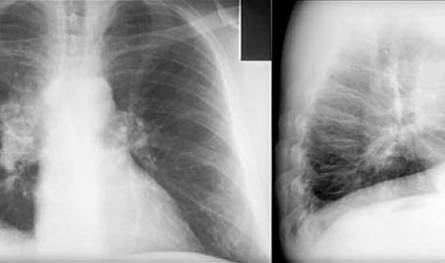

Vidverto Player

درس الباحثون بدايةً بيانات أكثر من 460 ألف شخص من سكان إنجلترا وكوريا الجنوبية وتايوان، وبيّنوا استناداً إليها وجود ترابط بين التعرض لتركيزات متزايدة من الجسيمات الدقيقة وزيادة خطر الإصابة بسرطان الرئة. إلا أن الاكتشاف الأبرز يتمثل في التوصل إلى فهم الآلية التي تتسبب من خلالها هذه الملوثات بسرطان الرئة لدى أشخاص من غير المدخنين.

وأثبت الباحثون من خلال دراسات مخبرية على الفئران أن الجسيمات أحدثت تغيّرات في جينين هما مُستقبِل عامل نمو البشرة (EGFR) وكيراس (KRAS) مرتبطين أصلاً بسرطان الرئة. من ثم حلل الباحثون نحو 250 عينة من أنسجة رئوية بشرية سليمة لم تتعرض إطلاقاً لمواد مسرطنة من التبغ أو التلوث الشديد. وظهرت طفرات في جين EGFR في 18 في المئة من العينات، وتغيرات في KRAS في 33 في المئة منها.